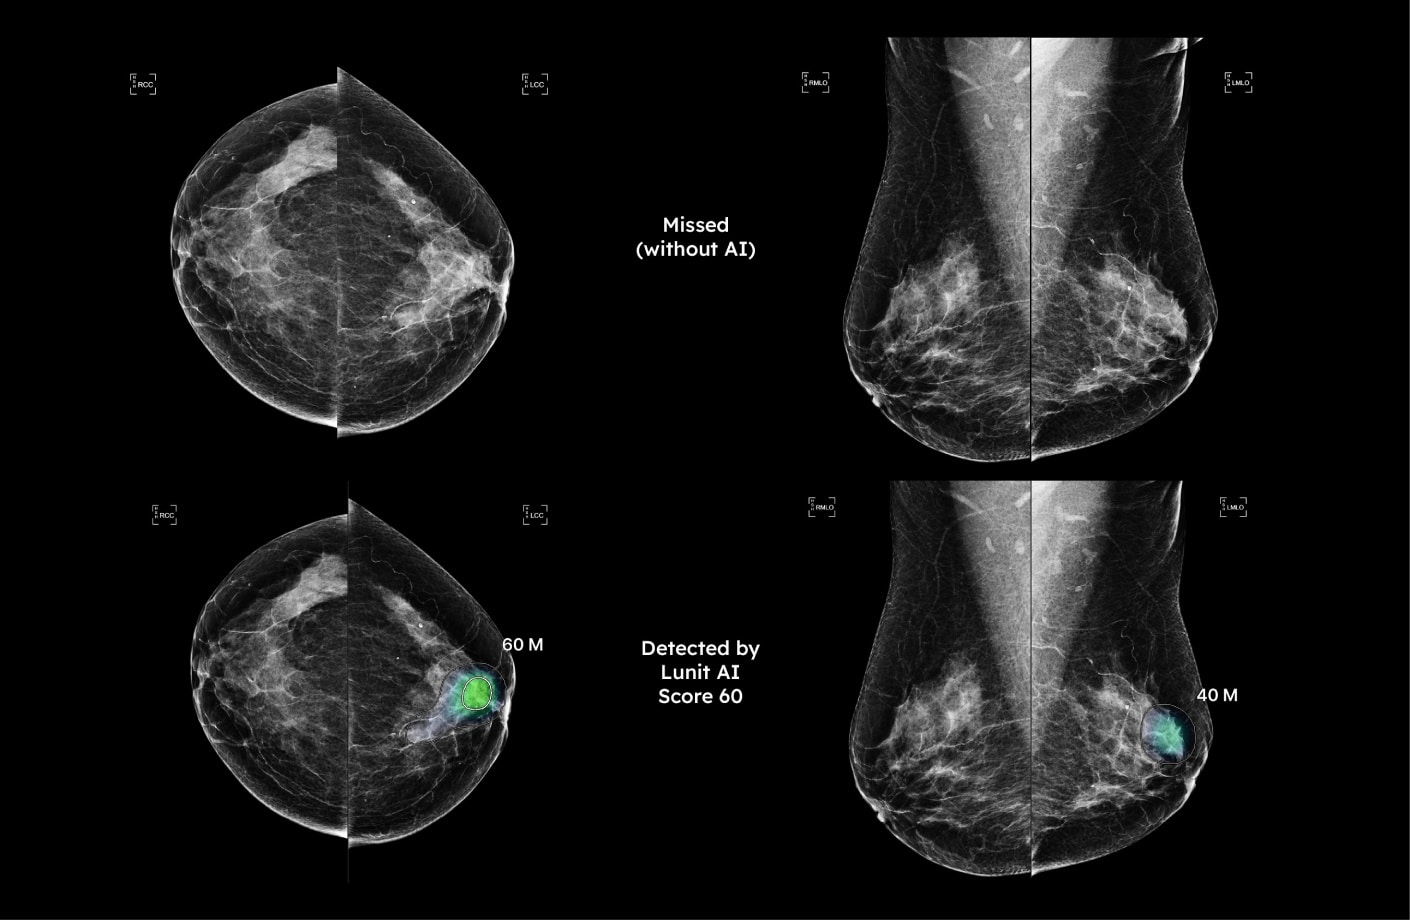

Lunit INSIGHT is an AI-powered software that analyzes mammogram images and alerts the radiologist of suspicious areas. Serving as a valuable second opinion, Lunit INSIGHT provides another layer of scrutiny and detects abnormalities that might not be visible to the human eye.